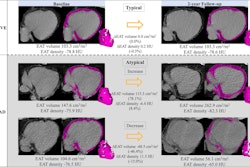

Images of epicardial adipose tissue segmentation in two male individuals with type 2 diabetes mellitus, aged 56 (individual 1) and 64 (individual 2) years, show volume differences less (upper two rows in A and B) or greater (lower two rows in A and B) than the mean volume difference of 16 mL between CT (in green) and MRI (in yellow). Deep learning was used for CT segmentation and semiautomated thresholding for MRI. (A) CT and MR images in the three-dimensional (3D) view. Both imaging modalities are presented from left and right views. (B) CT and MR images in the two-dimensional (2D) view. The stacked images consist of three selected 2D sections: cranial, mid, and caudal sections. All images are noncontrast images. Images and caption courtesy of the RSNA.